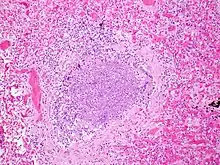

Acute inflammatory exudate occluding the lumen of the bronchiole and acute inflammation of part of the wall of the bronchiole